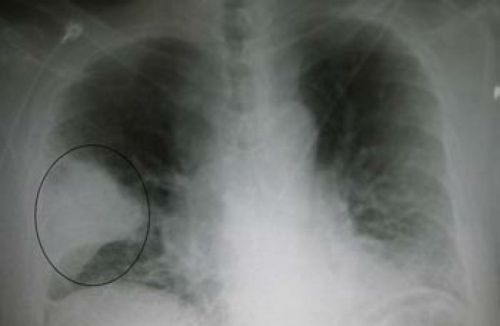

Пневмония

Острое воспаление легочной ткани вызывается бактериальной флорой, вирусами, грибковой инфекцией, паразитами. Наиболее часто сопровождается болями в правом подреберье крупозная пневмония. Изменения легочной ткани проходят четыре этапа:

Острая боль возникает в области лопатки, в других частях грудной клетки. Она способна иррадиировать в правое подреберье, живот. Боль усиливается при кашле, резких движениях, физической нагрузке. У пациентов повышена температура, одышка, откашливается мокрота с прожилками крови.

Диагноз подтверждается при перкуссии и аускультации легкого, на рентгенограмме. Имеются характерные изменения в крови, в анализе мокроты. Пневмонию лечат антибактериальными средствами или в зависимости от причины противогрибковыми и противовирусными препаратами.

Судя по снимку, поражена целая доля правого легкого, она полностью выключается из дыхания